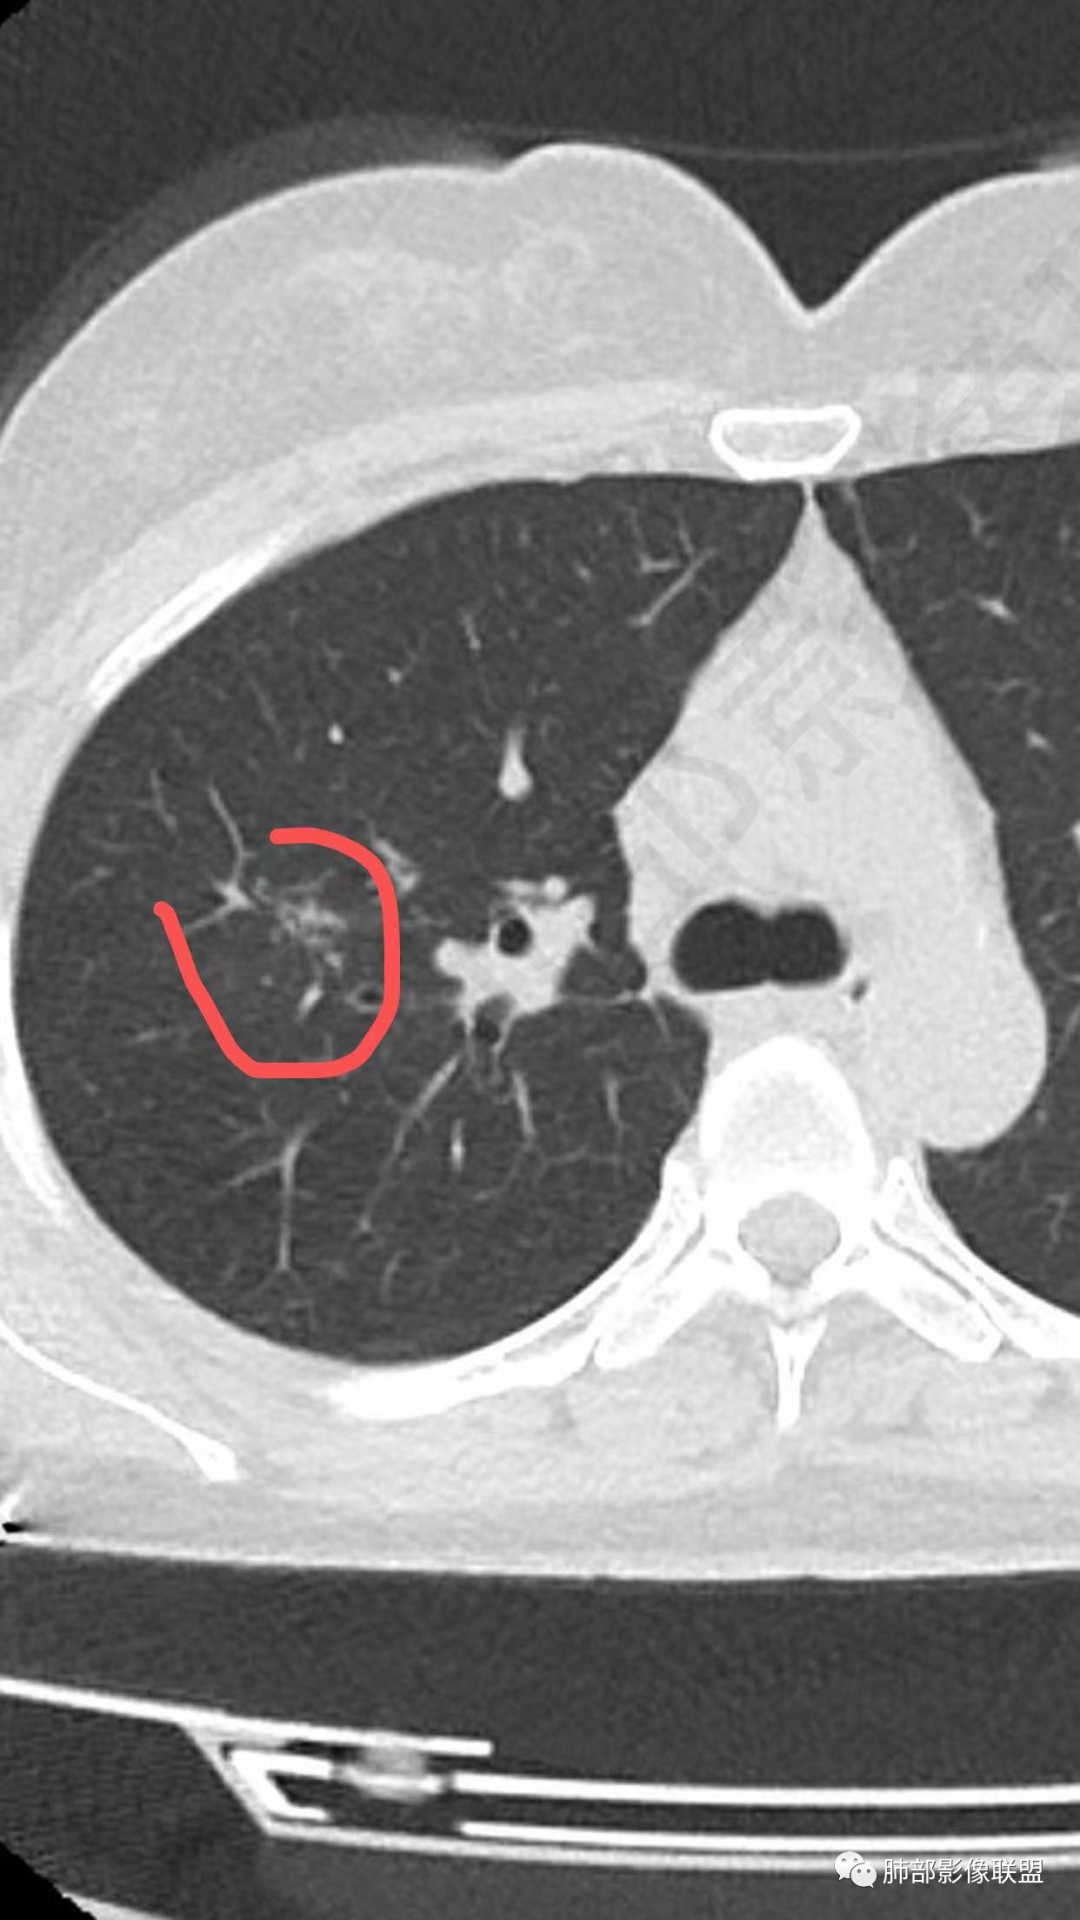

病例特点:52岁女性,体检患者。

影像特点:右肺上叶混合磨玻璃影,边界清晰,结构松散,内有多结节堆积及支气管扩张影,可见小叶间隔增厚,并局部增厚的小叶间隔上亦存在微结节,胸膜侧可见纤细索条,病灶周围可见多发微结节影。

总体分析:从病灶分布来看符合结核的好发位置,影像表现也符合结核的多态性,且出现卫星灶。由于有边界清晰的GGO,需要鉴别腺癌,虽然此病例有边界清晰的GGO,但是它的GGO的边缘有结节感,呈多结节堆积,而腺癌的GGO缺乏这种“多结节堆积感”,另外,此病例也没有发现腺癌的胸膜凹陷征、毛刺征及月牙铲等。

右肺上叶不规则磨玻璃密度结节(内小结节堆积感明显),边缘清,内可见扩张支气管,见胸膜牵拉,牵拉线纤细、柔软,右肺中叶斑片影,左下肺胸膜下多发小结节。首先考虑结核,鉴别腺癌。